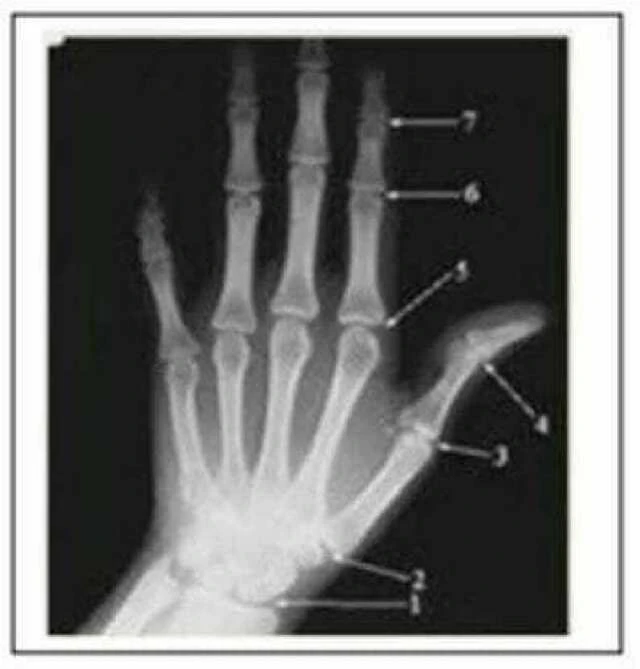

e. Phim cổ tay: sử dụng để xác đinh tăng trưởng đang còn ở bệnh nhân. Phim này là tiêu chuẩn củaMỌI trường hợp bệnh nhân hạng III đang còn tăng trưởng